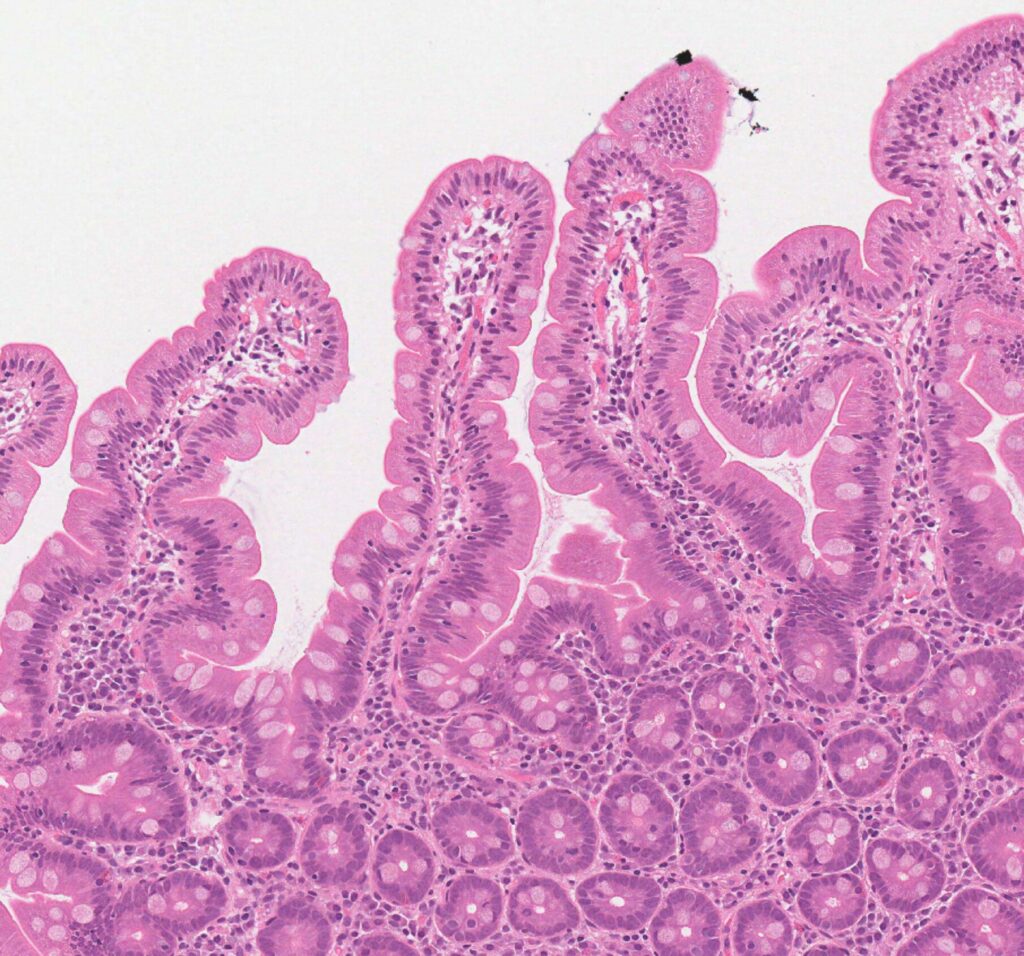

- Imaging and Biopsy Data: Where available, the AI cross-references visual data from scans and biopsy slides to detect subtle patterns indicative of intestinal damage.